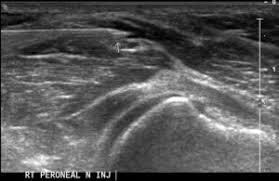

- Τεχνική Hydrodissection υπό υπερηχογραφική καθοδήγηση, όπου απελευθερώνεται το νεύρο από τις συμφύσεις με χρήση φυσιολογικού ορού υπό πίεση